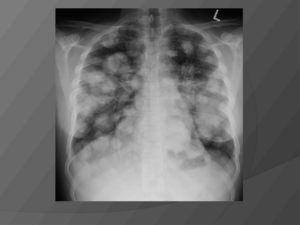

| Стадия рака | Описание | Рак легких на рентгене |

| Первая | Первая стадия рака легких подразделяется на две группы:1А — опухоль не более 30 мм в диаметре.1В — опухоль не более 50 мм в диаметре.На первой стадии еще нет метастазов, а значит опухоль можно удалить полностью или излечить с помощью лучевой терапии.Шанс на выздоровление составляет 73%.К сожалению, явных симптомов на этой стадии нет, поэтому очень трудно распознать самому. | Как выглядит рак легких: |

| Вторая | 2А — размер достигает 50 мм.2В — до 70 мм.Метастазы могут уже поваляться рядом с легкими, но еще не достигли лимфоузлов. Тень лимфатических узлов можно увидеть на рентгенологии.Выживаемость значительно ниже чем на 1 стадии. Вылечиваются только треть онкобольных. | |

| Третья | 3А- опухоль достигает не менее 70 мм.3В- опухоль более 7 мм.В процессе разрастания опухоли уже затрагиваются лимфоузлы и поражает их, а также опухоль может затрагивать и другие органы и метастазировать в них. Могут поражаться такие органы как: сердце, трахея, печень, кровеносные и лимфатические сосуды. | |

| Четвертая | 4 стадия карциномы легких уже не подлежит лечению и заканчивается летальным исходом. У пациента сильные и мучительные боли. Метастазы проникают в другие органы и уже появляются сопутствующие заболевания. |

При центральной форме ракового образования, на рентгенографии будет отображаться, что в легких присутствует расширенная сеть сосудов, а также имеются замутненные участки. Когда у легочной онкологии периферический характер, картина на рентгеновском изображении будет отображать присутствие четкой тени с неровными краями, от которой к корню легких отходят отростки в виде лент.

При расположении онкообразований в поверхностных слоях органа или же возле места входа главного бронха флюорография выявляет рак в виде темного пятна неясной этиологии.

Если врач-рентгенолог при плановом посещении пациента обнаруживает на снимке такие пятна, он направляет пациента на рентген в двух проекциях или же на компьютерную томографию с целью получить более точные снимки.

Будет виден ли рак на флюорографии при другом расположении раковой опухоли? Если процесс начал развиваться в глубине легких, флюороснимок не будет информативным, и потребуются другие способы.